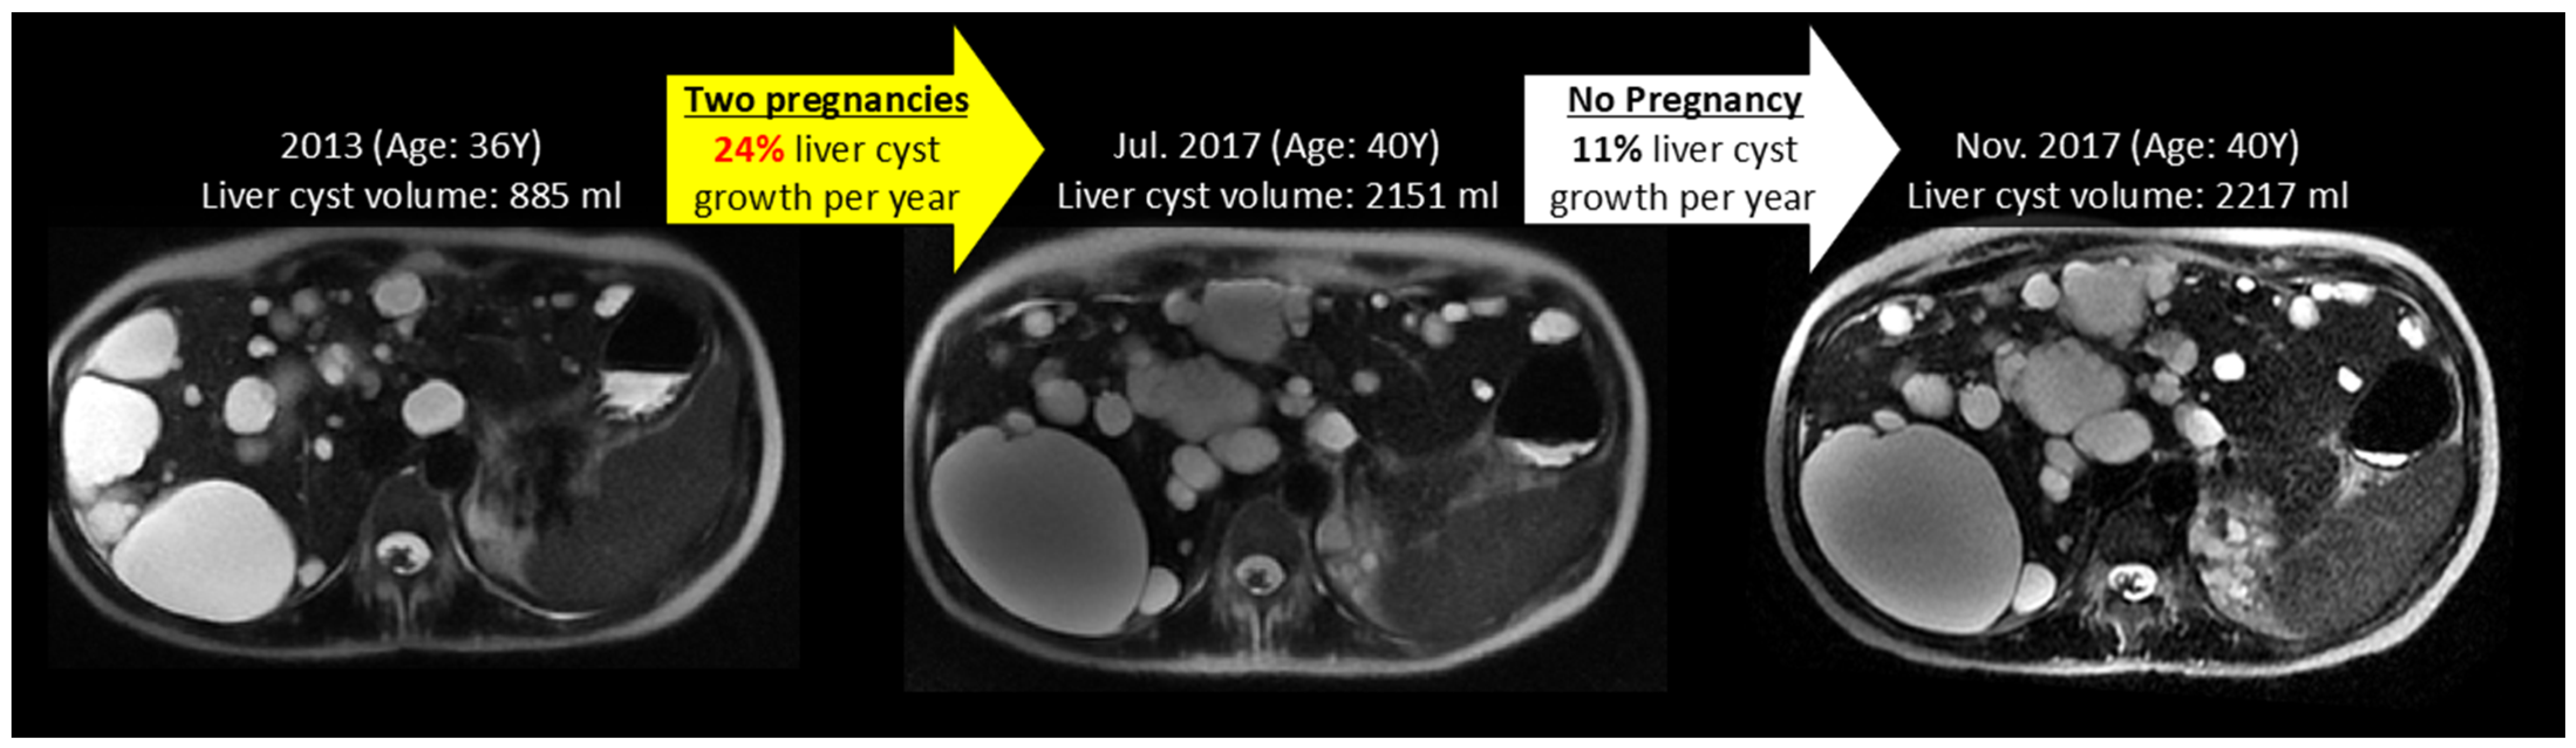

| Liver cyst volume | ADPKD | 34 ± 16 | 23 ± 17 | 0.005 |